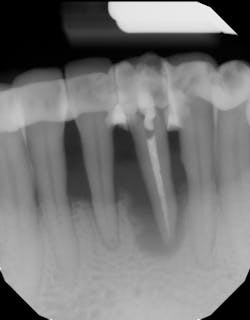

- Appropriate scaffolding material, biologic agent, and/or cell occlusive barrier for periodontal regeneration (figure 4)

- Follow-up hygiene appointments every three months or less to ensure long-term result (figures 6 and 6a)